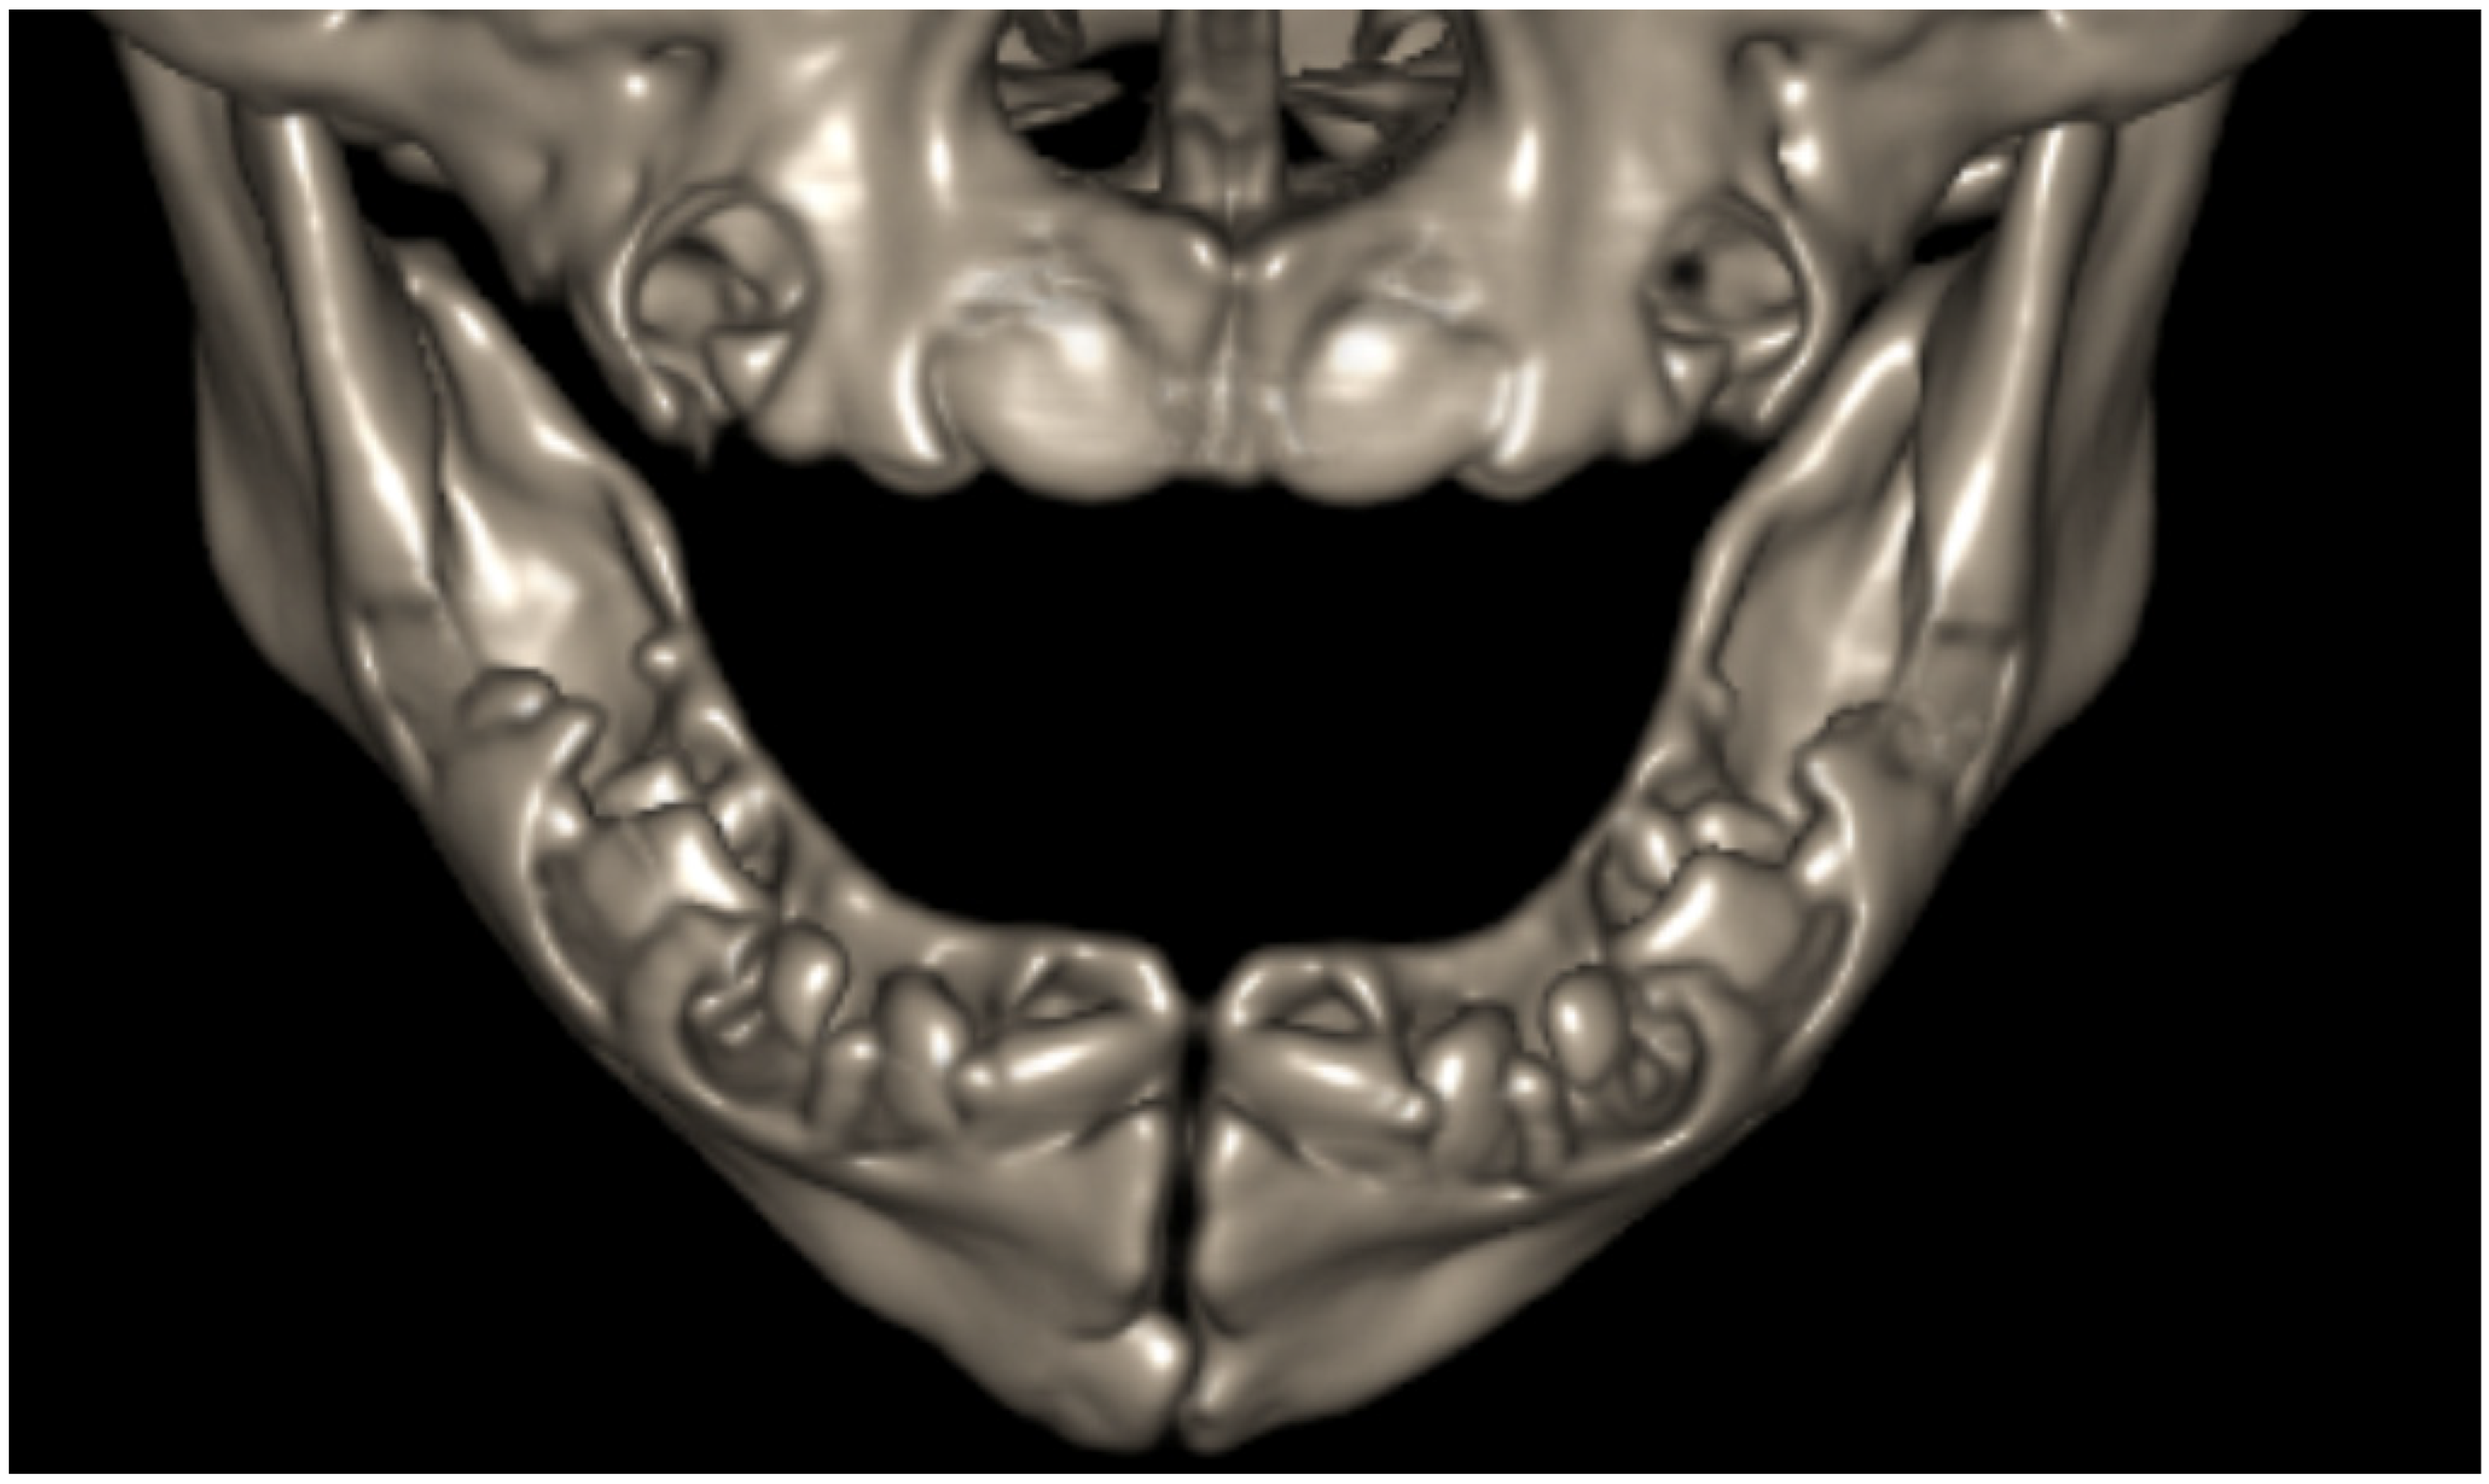

3.1. Anatomy of the Dental Arch

3.1.1. Anatomy of Tooth Structure

3.1.2. Periodontal Tissues